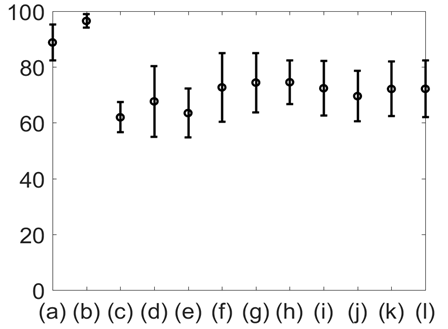

The average respiratory rate was calculated for all the signals of interest and all 12 subjects. This is plotted in Figure 8. The results shown in Figure 8 suggest that the average respiratory rate was 14 with standard error of 4 breath per minute. Subsequent analysis suggested that the overall accuracy in detecting respiratory rate using all modalities varied between 85-100% with GSR having the highest in accuracy (100%). The %Phase match for each test signal for 8 subjects is plotted in Figure 9.

Figure 8 Average respiratory rate with standard error for: (a) Lung volume change; (b) Chest wall movement; (c) GSR; baseline wonder of: (d) SCG-craniocaudal, (e) SCG-lateral, and (f) SCG-dorsoventral; amplitude modulation for: (g) SCG-craniocaudal; (h) SCG-lateral; and (i) SCG-dorsoventral; and frequency modulation for: (j) ECG, (k) SCG-craniocaudal, (l) SCG-lateral, and (m) SCG-dorsoventral signal for all 12 subjects. The average respiration rate was found to be around 14 with a standard error of 4 breath per minute.

Figure 10 shows the mean and standard deviation of %Phase match values of the different physiological signals with respect to lung volume. The results shown in Figures 9 & 10 indicate that the %Phase match values for different test signals varied from about 50% to 98%. The GSR signals showed the highest accuracy in the %Phase match (approximately 94%-98%) for all cases. The chest wall movement and SCG baseline wondering (in the craniocaudal, lateral, and dorsoventral directions) waveform also showed promising results (approximately 85%-94%, 70%-85% ,65%-90%, 65%-85% respectively).

Figure 10 Mean and standard deviation of %Phase match for: (a) Chest wall movement; (b) GSR; baseline wonder of: (c) SCG-craniocaudal, (d) SCG-lateral, and (e) SCG-dorsoventral; amplitude modulation for: (f) SCG-craniocaudal, (g) SCG-lateral, and (h) SCG-dorsoventral , and frequency modulation for: (i) ECG, (j) SCG-craniocaudal, (k) SCG-lateral, and (l) SCG-dorsoventral signal for all 12 subjects. The chest GSR (b) had the highest ageement with the gold standard.